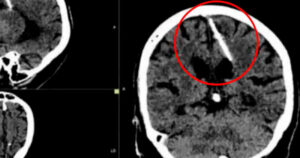

Médicos detallaron que el objeto estuvo alojado en su cerebro desde su nacimiento y explicaron que es probable que sus padres hayan trataron de matarla en su infancia